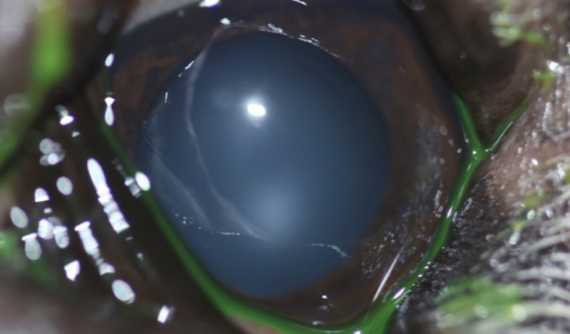

Brutus mostraba un crecimiento irregular sobre la superficie de su ojo derecho.

Tras la exploración oftalmológica completa realizamos una OCT de córnea y una ecografía UBM para valorar apropiadamente la masa y su profundidad.

También decidimos tomar una muestra para biopsia.